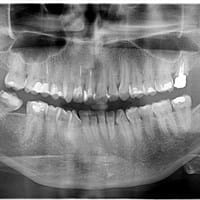

¿Cómo se ve el agujero palatino anterior en radiografía?

Quisiera saber si ¿Es normal que aparezca como una sombra negra en la zona del orificio palatino anterior o si la sombra es le mismo?